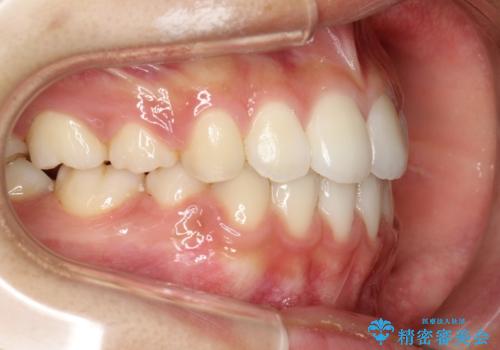

前歯が八重歯でガタガタ ワイヤーによる抜歯矯正